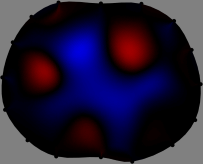

Figs. 3 and 4 compare the performance of the proposed FER method in (20) with the standard regularized least-squares method ((19) when \mathcal{R} is the identity matrix). The regularization parameter of the standard method was heuristically chosen for its best performance, and the parameter of the FER method was set to be one of three different values λ=0.05,0.2,𝜆0.050.2\lambda=0.05,0.2,\infty. The injection current was 1 mARMSRMS{}_{\tiny{\mbox{RMS}}} at 100 kHz, and the frame rate was 9 frames per second. The reference frame at t0subscript𝑡0t_{0} was obtained from the maximum expiration state. The measured data, 𝐕˙(tm)˙𝐕subscript𝑡𝑚\dot{\mathbf{V}}(t_{m}), represent the voltage differences between each time tmsubscript𝑡𝑚t_{m} and t0subscript𝑡0t_{0}. The blue regions, which denote where conductivity decreased by inhaled air, increased during inspiration and decreased during expiration. The FER method with λ=𝜆\lambda=\infty was clearly more robust than the standard method that produced more artifacts originated from the inversion process.

Figure 3: The reconstructed images of the conductivity change of the subject A by the standard regularized least square method and the proposed fidelity-embedded regularization (FER) method for three difference values λ=0.05,0.2,𝜆0.050.2\lambda=0.05,0.2,\infty. Here, the time step is 0.22 seconds (tm+2tm0.22subscript𝑡𝑚2subscript𝑡𝑚0.22t_{m+2}-t_{m}\approx 0.22).

Figure 4: The reconstructed images of the conductivity change of the subject B by the standard regularized least square method and the proposed fidelity-embedded regularization (FER) method for three difference values λ=0.05,0.2,𝜆0.050.2\lambda=0.05,0.2,\infty. Here, the time step is 0.55 seconds (tm+5tm0.55subscript𝑡𝑚5subscript𝑡𝑚0.55t_{m+5}-t_{m}\approx 0.55).